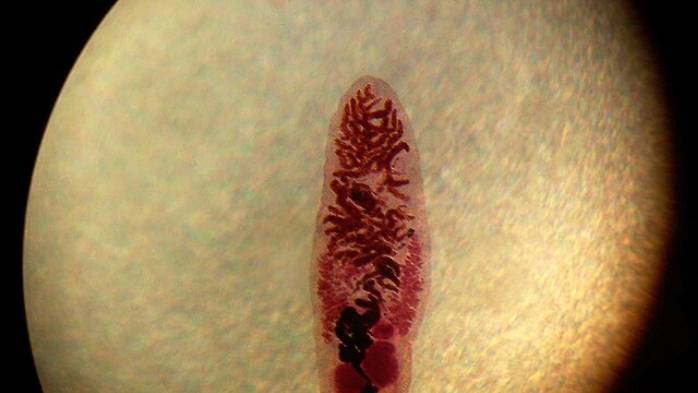

ДИКРОЦЕЛИОЗ - возбудитель, морфология, цикл развития, диагностика, профилактика, лечение